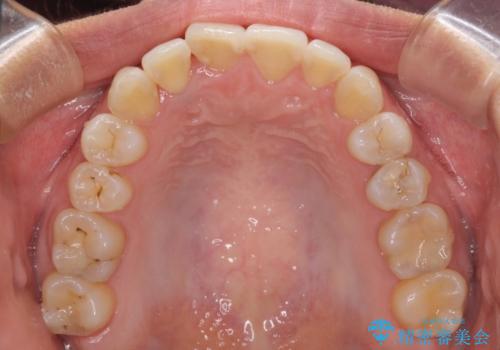

前歯のデコボコをインビザラインでスッキリと仕上げる

- 上下前歯のデコボコと奥歯の銀歯を気にして来院された患者様です。

口元をインビザラインにより歯列を整え、その後に失活している奥歯をオールセラミッククラウンにて補綴治療することとしました。

長時間のマウスピース装着に協力いただき、自然な口元に仕上げることができました。

気になっていた銀歯もオールセラミッククラウンで本物の歯のようになり、患者様には大変満足していただきました。